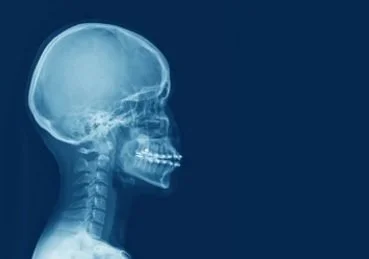

Bones of the Head and Neck Region

The bones in the region of the head and neck can be categorized as:

- Bones of the skull- this can be further divided into: - Bones of the neurocranium

- Bones of the viscerocranium

- Bones of the neck